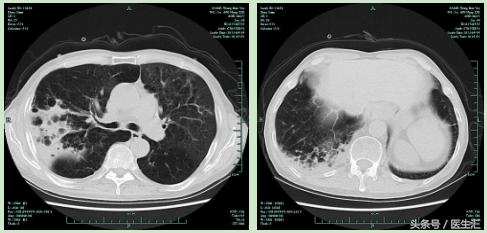

【肺CT】

【提示】该患者有COPD病史,但是本次住院有发热,肺CT上表现为右上肺后段及右下方基底段渗出实变病灶,因此应该考虑为肺炎,由于其在当地医院住院期间发生肺炎,因此诊断医院获得性肺炎